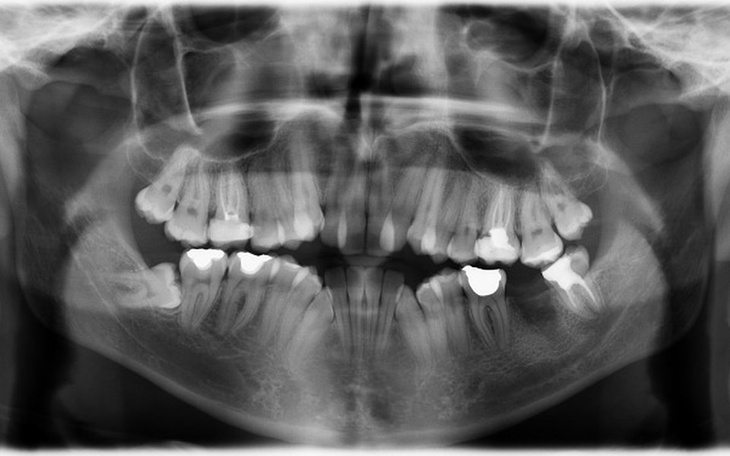

Cześć wszystkim. Mam na imię Kamil. Jestem dwudziestoletnim studentem z Lublina. Założyłem tę zbiórkę z nadzieją, że przy Waszej wspólnej pomocy uda mi się pokonać moje lęki, wstyd, strach i niepewność. Moim problemem jest konieczność założenia aparatu ortodontycznego. Oprócz znacząco widocznych, krzywo rosnących zębów z przodu, cierpię również na zgryz otwarty częściowy przedni, a także tyłozgryz, przez co rysy mojej twarzy nie są do końca naturalne, przez cofniętą dolną szczękę. Muszę przyznać, że o ile sama część leczenia ortodontycznego jest jasna i klarowna, o tyle czeka mnie również jeszcze leczenie stomatologiczne. Niestety odkąd byłem mały, nie miałem zbytnio szczęścia do stomatologów, którzy przez niedbałość zamiast leczyć moje zęby tylko pogarszali sprawę. Moje kompleksy ze względu na krzywe zęby występują już od czasów podstawówki, gdzie nieraz mogłem spotkać się z nieprzyjemnymi spojrzeniami w moją stronę z tego powodu. Nieukrywam, że obecnie staram się kryć moją wadę jak tylko mogę, otwierając buzię jak najmniej mogę, ale powoduje to, że mówię coraz to bardziej niewyraznie, a także seplenię. Chiałbym już raz na zawsze skończyć ten etap, zwłaszcza w momencie życia, w którym jestem gdzie kontakty międzyludzkie są bardzo ważne, a w moim przypadku są one zaburzone, bo po prostu się wstydzę. Obecnie uczęszczam do jednego z najlepszych ortodontów w Polsce, lecz nieukrywam, że wraz z profesjonalizmem, idą wysokie koszta zabiegów. Jedna wizyta stomatologiczna kosztuje mnie conajmniej 300 złotych, a czeka mnie takich jeszcze 5 lub 6. Potem dochodzi już leczenie ortodontyczne. 200 złotych za każdą wizytę kontrolną co 8 tygodni no i sam aparat. Udało mi się samemu już częściowo na niego zarobić, ale w stosunku do całego kosztu leczenia jest to niewiele. Bardzo prosiłbym o Waszą pomoc. Jest to dla mnie szczególnie istotne, ponieważ chciałbym bardzo przeżyc moment, w którym będę miał już upragniony aparat na zęby. Umieścilem tutaj tylko zdjęcie tomograficzne moich zębów. Jeśli jednak ktoś zainteresowany jest obejrzeniem zdjęć pokazujących moją wadę na zdjęciach, jestem w stanie wysłać je na e-mail'a.